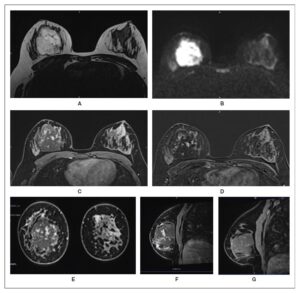

Initial ultrasonography revealed a heterogeneous 3.5 × 2 cm mass, and cytology suggested a benign hemorrhagic–inflammatory lesion (Figure 1). After a course of antibiotics, follow-up MRI demonstrated a well-demarcated 6 × 4 × 4.5 cm mass with T2 hyperintensity and diffusion, features compatible with an abscess (Figure 2). The lesion also showed progressive, atypical contrast enhancement, prompting further sampling. Microbiopsies revealed benign granulation tissue undergoing fibro-hyaline organization with telangiectatic vascular clefts (Nottingham Class B2).

Repeat breast MRI showed that the lesion had grown to 6 × 5 × 6 cm (Figure 3). It appeared well-defined on T2-weighted imaging, with marked diffusion hypersignal and no axillary lymphadenopathy. Angiosarcoma became a primary diagnostic consideration. A second biopsy confirmed the diagnosis of a well-differentiated, low-grade primary angiosarcoma of the breast (Figure 4). Thoraco-abdominal CT and PET-CT revealed no distant metastases, and the lesion showed no FDG uptake on PET-CT.

This case report highlights the challenges involved in diagnosing and treating PAB. In young women, a painful breast mass is rarely initially suspected to be PAB, particularly when MRI findings suggest a poorly vascularized lesion, which may be misinterpreted as a breast abscess. However, lack of response to antibiotic therapy should prompt timely reassessment of the diagnosis. In this case, diagnostic uncertainty was further compounded by discordance between imaging findings and biopsy results, likely related to the low-grade nature of the tumor. Histologically, this tumor is characterized by anastomosing, irregular, non-atypical vascular channels that infiltrate the surrounding breast tissue [1,2]. On dynamic MRI, low-flow vascular channels may appear as a “blood-filled sponge,” accounting for the marked T2 hyperintensity observed, rather than representing purulent necrosis as initially interpreted.

Breast MRI is the preferred imaging modality, typically demonstrating low signal intensity on T1-weighted images and high signal intensity on T2-weighted images, with variable enhancement and washout patterns depending on tumor grade [5,6,9,10]. In young patients presenting with rapidly progressive breast masses, MRI should be considered the imaging technique of choice, particularly for large lesions, as it facilitates earlier diagnosis and more timely therapeutic intervention, which may ultimately improve clinical management and prognosis. PET-CT and CT are primarily used for staging purposes; however, definitive diagnosis relies on histopathological examination [3]. Fine-needle aspiration is limited by a high false-negative rate of approximately 37%, while core needle or macrobiopsy may be technically challenging because of the highly vascular nature of the tumor [1,3,8].